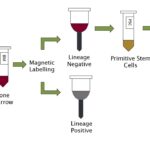

Maintenance and expansion of myeloid progenitor cells in 3D culture

This study aimed to find a better treatment of Myelodysplastic Syndrome using myeloid progenitor cells grown in 3D culture.

Posted by John Lee on Wednesday, December 23rd, 2020 in May 2020, 3D Culture, Myelodysplastic Syndrome, myeloid cells